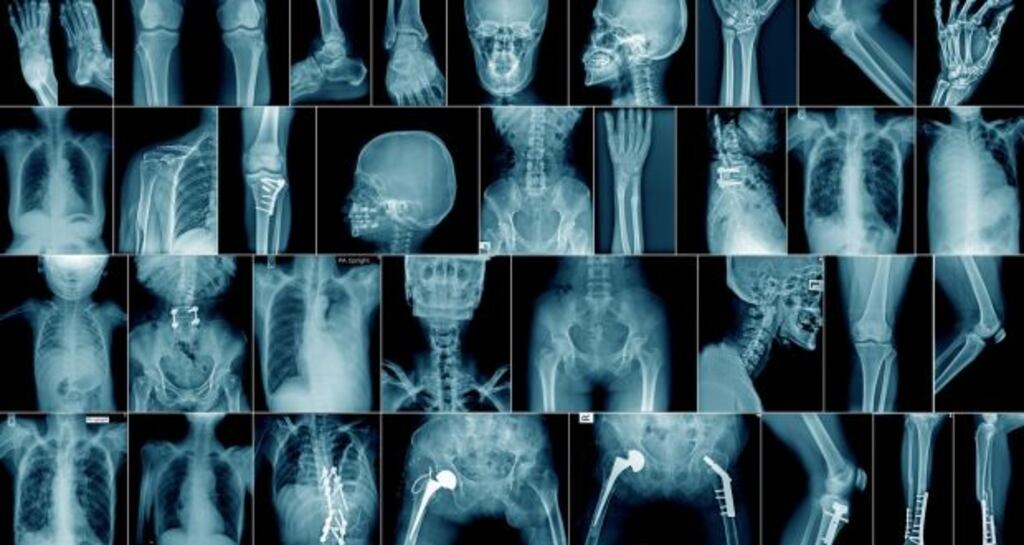

Kashimbo Musonda, who allegedly mistook a knee X-ray for an elbow, is facing allegations of poor professional performance and professional misconduct. They relate to events at University Hospital Waterford over a 2½-week period to March 8th, 2017.

On Wednesday the committee heard expert opinion on X-rays taken by Ms Musonda of 23 patients, which raised a number of issues including the over-exposure or unnecessary irradiation of parts of people's bodies.

Eileen Kelly, radiography services manager at University Hospital Galway, gave her opinion on numerous X-rays taken by Ms Musonda.

In one case, involving an 18-month-old girl, she explained an X-ray of the pelvis led to a significant portion of her body outside the “area of interest” being unnecessarily exposed. Part of the hands of the girl’s carer were also exposed. Other X-rays demonstrated poor image quality.

Among her assessment of competence in several areas of Ms Musonda’s work, Ms Kelly said allegedly mistaking a knee for an elbow – had she examined the image as opposed to merely glancing at it – would amount to professional misconduct.

“A knee and an elbow are very different joints and no radiographer in my experience would ever mistake one for the other,” she said.